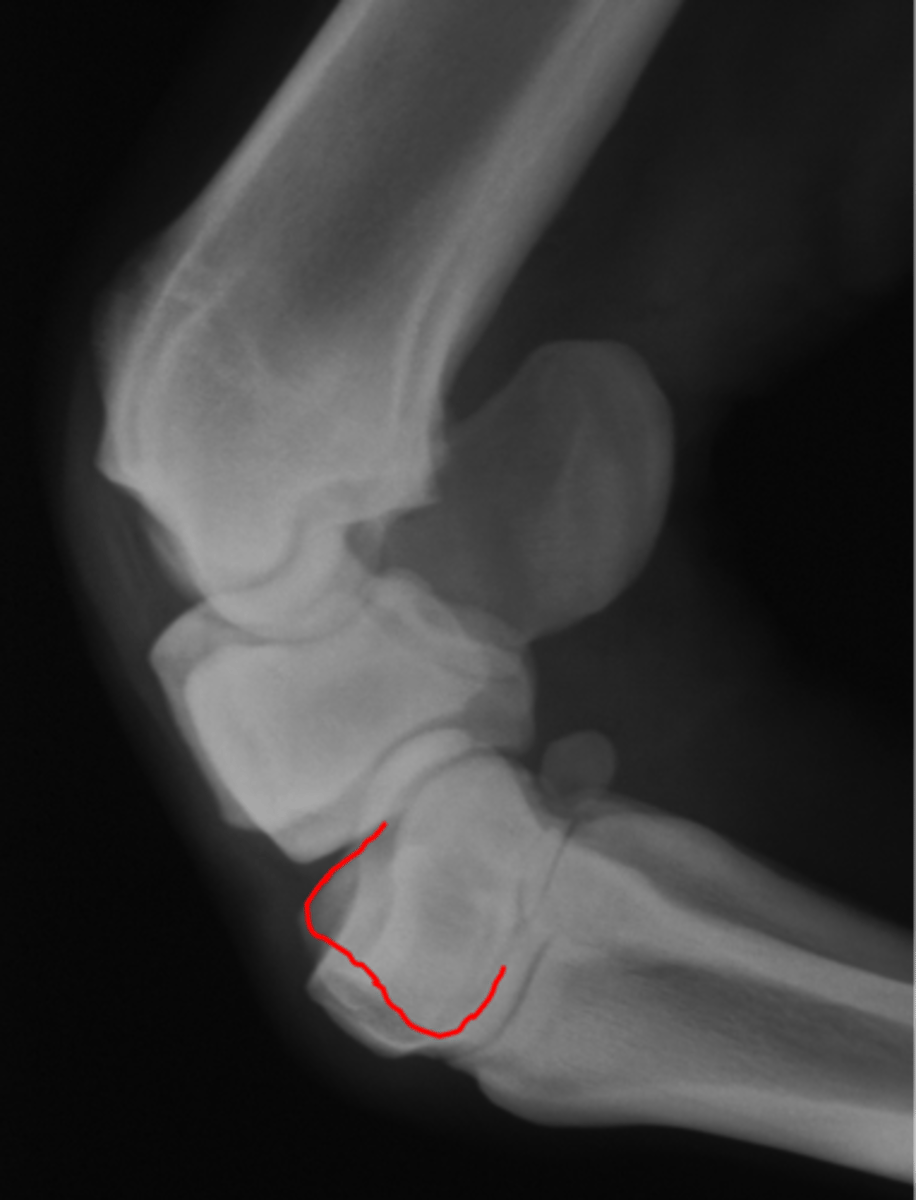

Short pastern (P2)

Long pastern (P1)

Pastern joint (proximal interphalangeal joint)

Distal sesamoidean ligament

What attaches at EOP?

Collateral ligament of the coffin joint

What attaches at EOP?

Long pastern (P1)

Short pastern (P2)

Medullary cavity

Ergot

Collateral ligament of the coffin joint

What attaches at EOP?

Nutrient foramen of P2

Extensor process of P3